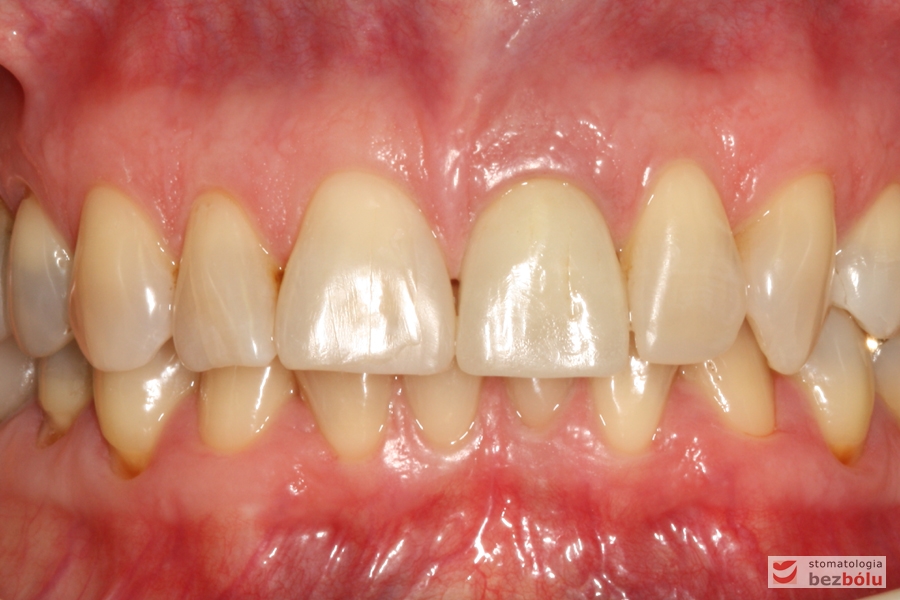

Do naszej placówki zgłosiła się starannie planująca swoje działania Europejka, mieszkająca na stałe w Kotlinie Jeleniogórskiej. Jej oczekiwania dotyczyły bardzo metodycznie zaplanowanego planu leczenia. Celem jaki postawiła przed naszym zespołem lekarzy było wyeliminowanie wszystkich wątpliwych i nierokujących wypełnień, a także poprawa estetyki w zakresie lewego siekacza centralnego w szczęce. Został rozpisany blisko dwuletni plan wymiany zużytych i nieszczelnych wypełnień amalgamatowych i kompozytowych. Zaplanowano również przygotowanie endodontyczne wybranych zębów w szczęce i żuchwie, a także zaopatrzenie w inlay’e porcelanowe i korony ceramiczne wykonane w systemie e-max.